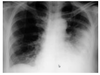

what’s wrong?

- Infection of the Left lung (LLL and LUL)

- White pus

- Bronchiae are more visible due to an interference between tissue and pus

**note the RUL pneumonia also and a horizontal fissure

this person is shunting blood into the left lung, and so not getting mych oxygen around their body, you can see the ventilatory wire

Pneumonia of the LLL and the diaphragm is really hard to follow!

Somes a lateral view is helpful too.

If their is no lung-diaphragm interface, it’s a lower lobe infection!